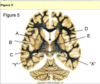

temproal field is missing thus probably this a lesion to the chiasm. information from temporal visual field enters nasal retina and must cross in the chiasm

this is a pituitary adenoma that is putting pressure on the chiasm leading to a bi-temporal hemianopia (temporal fields missing

lesion to the optic tract leading to a field defect in both eyes. a nasal on right and temporal on left

demyelinating plaque that is affecting the optic tract